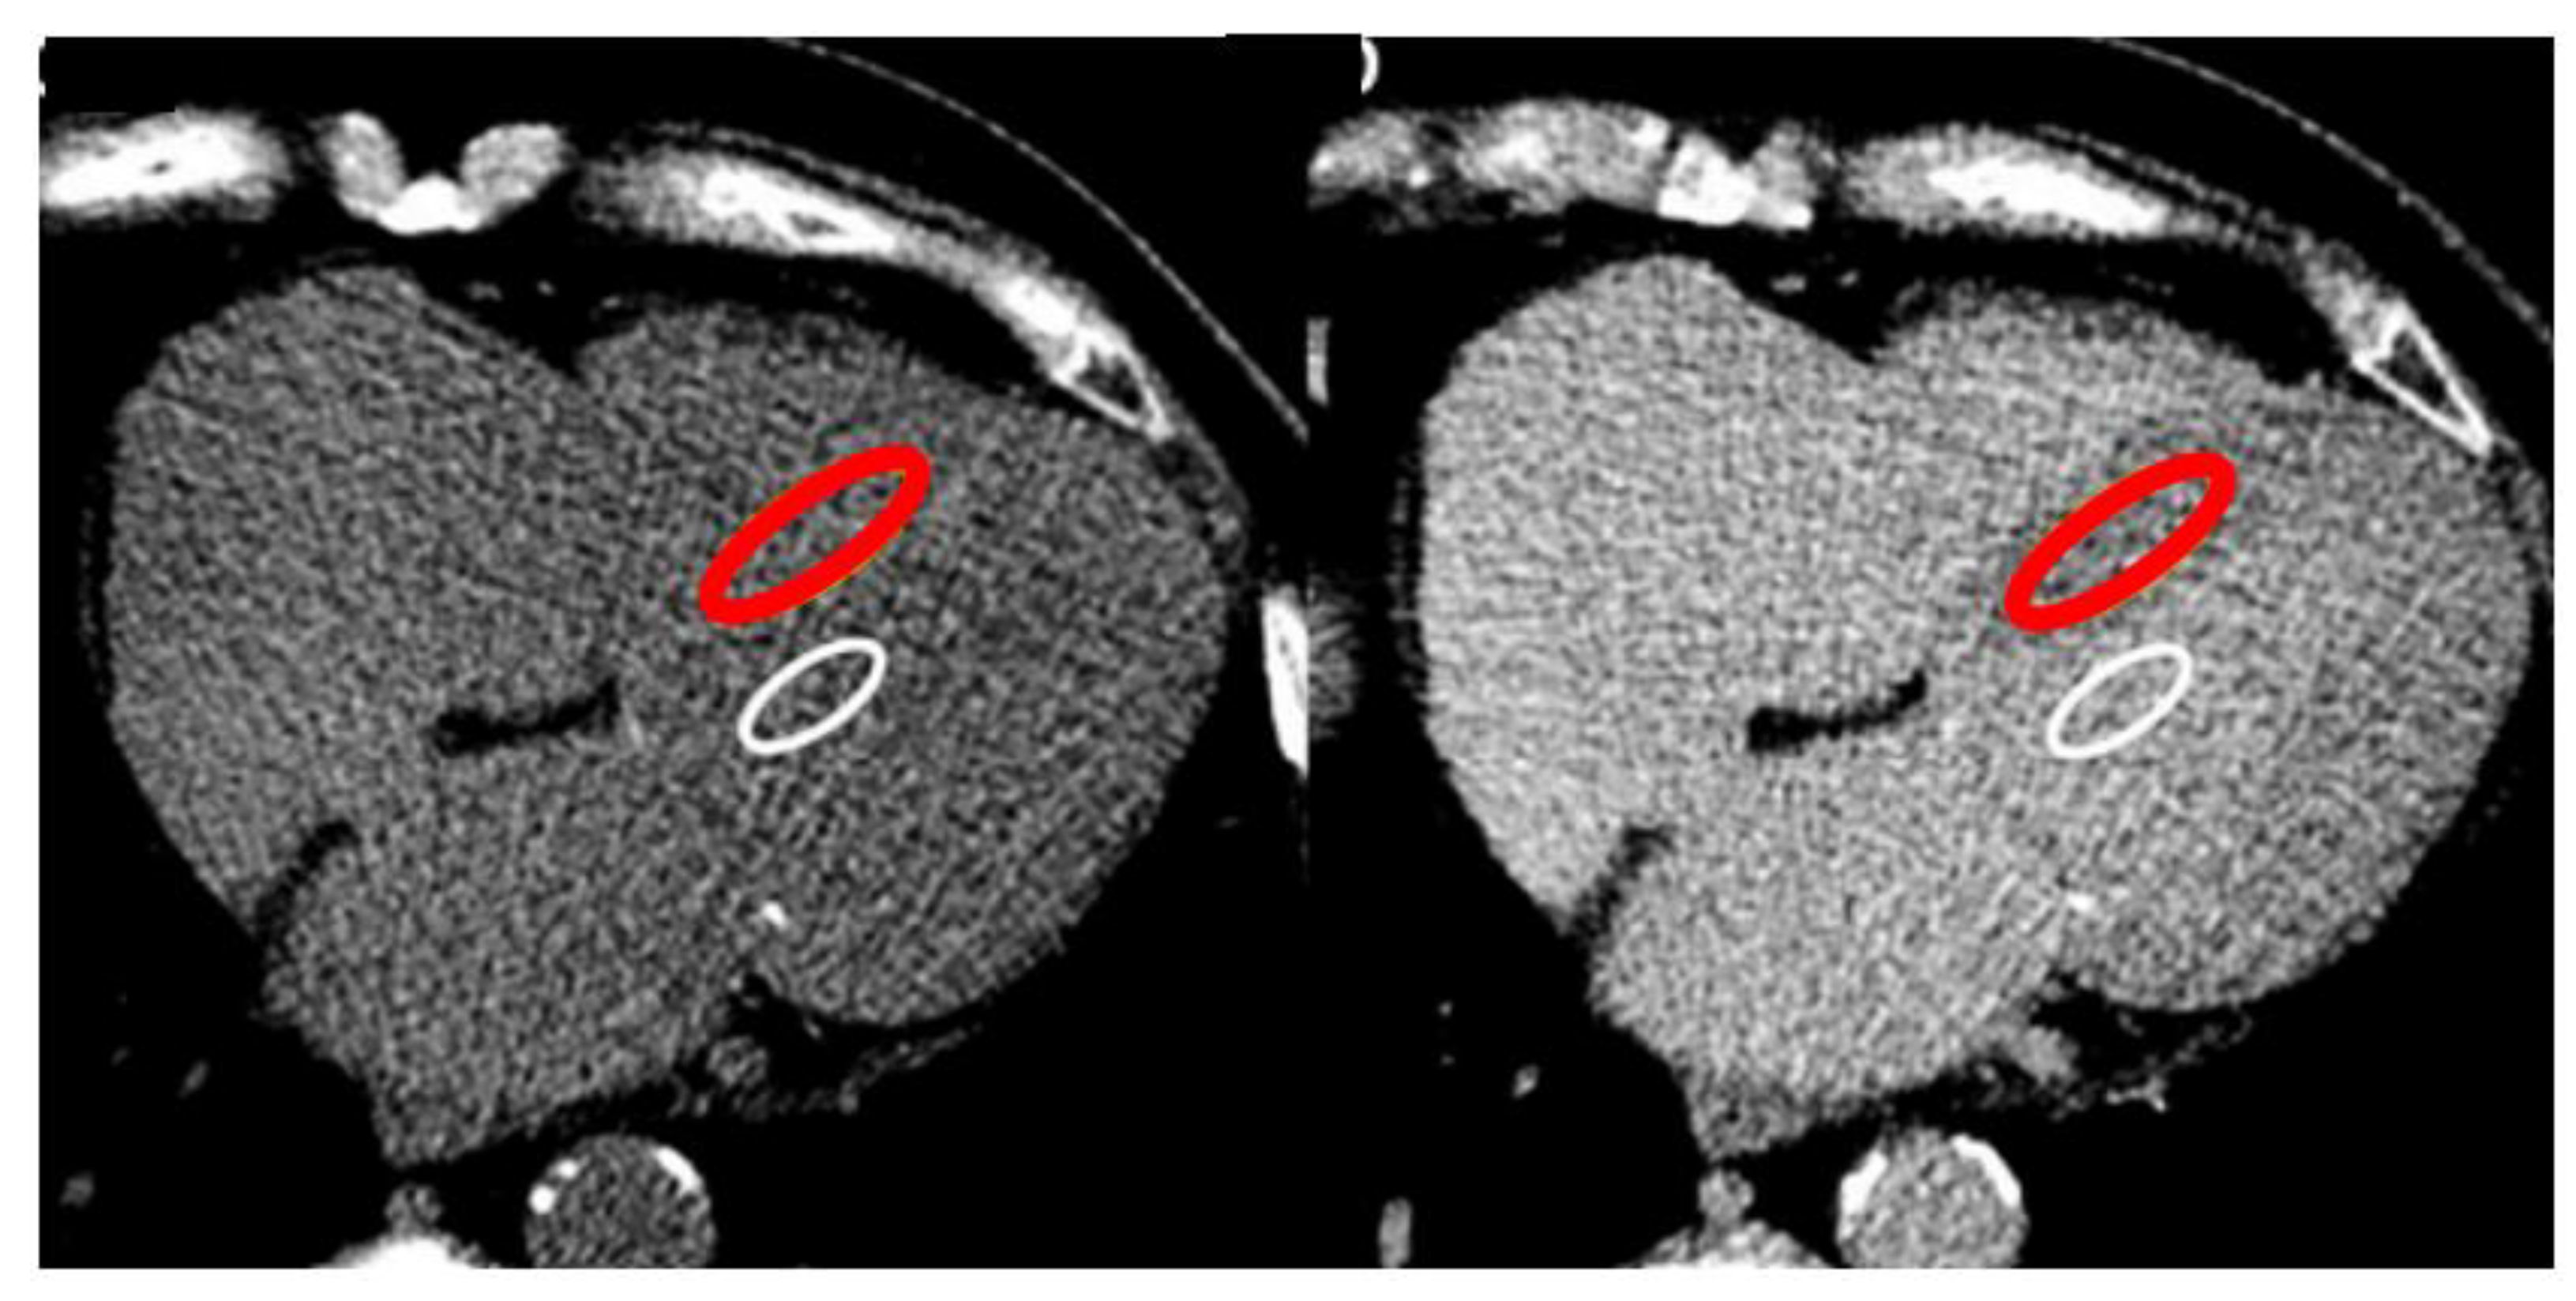

It’s suggested to draw polygonal wide ROI to include the greatest area of myocardial septum but avoiding the endocardial edge and therefore partial voluming, and a wide ROI for the blood pool away from papillary muscles (Figure 2).

Figure 2. Single-energy ECV-CT. Pre-contrast scan (left) and post-contrast scan (right) lead to derive ROIs into the blood pool and the myocardium, for the calculation of ECV-CT by dedicated equation.